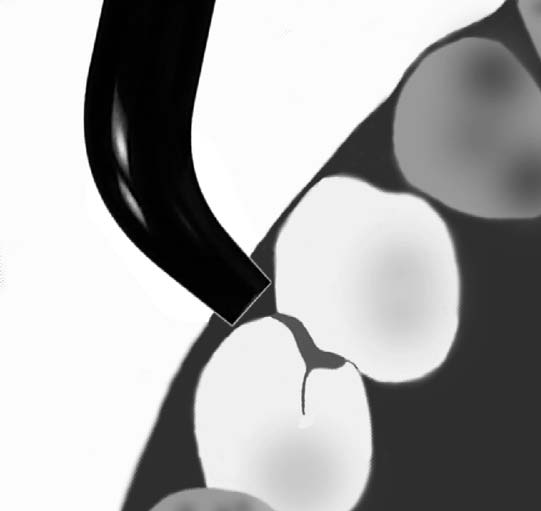

Transiluminación dentaria

La transiluminación antes de la aparición de la "tecnología led" solo era utilizada para la detección de caries proximal en los incisivos. En la actualidad dada la potencia lumínica de dichos dispositivos puede ser utilizada para la pesquisa de caries proximal y oclusal de la piezas dentales posteriores. Se utiliza una  lámpara led de luz día ( 5500 ºK)  con su fibra óptica, como se muestra en la fotografía inferior derecha.

La luz visible es enviada por medio de una  fibra óptica hasta la superficie del diente, dónde se propaga  a través del tejido hasta la superficie opuesta. El resultado  es una imagen que resulta de la distribución de la luz a en el interior d e la pieza dental. (1) Un proceso de caries en esmalte y dentina tiene la particularidad de un cuerpo opaco de reflejar la luz, en consecuencia la observación en la superficie opuesta generaría una imagen oscura.

Un ojo bien entrenado y la práctica clínica puede complementar el diagnóstico visual de caries inicial y moderada en premolares y molares.

¿Caries inicial ó moderada?

En apariencia cuando aplicamos luz, se mantiene el color gris. Pero cambiando el eje de luz, podemos ver el espesor de la sombra gris.

Sospechamos de una caries moderada por la amplia sombra gris.